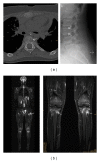

Chronic nonbacterial osteomyelitis (CNO) with its most severe form chronic recurrent multifocal osteomyelitis (CRMO) is a non-bacterial osteitis of yet unknown origin. Secondary to the absence of both high-titer autoantibodies and autoreactive T lymphocytes, and the association with other autoimmune diseases, it was recently reclassified as an autoinflammatory disorder of the musculoskeletal system. Since its etiology is largely unknown, the diagnosis is based on clinical criteria, and treatment is empiric and not always successful. In this paper, we summarize recent advances in the understanding of possible etiopathogenetic mechanisms in CNO.